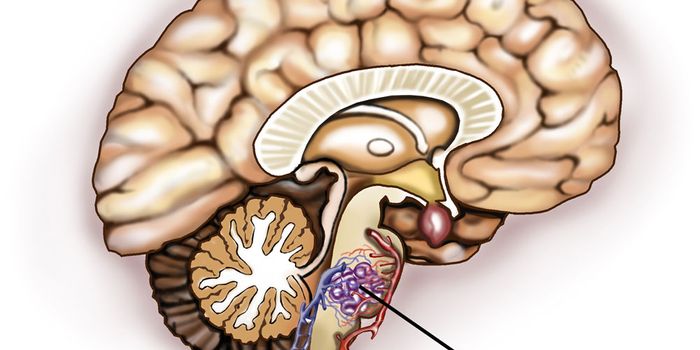

FEB 13, 2015NeuroscienceWhile tens of millions of people have abnormal, leak-prone sproutings of blood vessels in the brain called cerebral cave ...

-